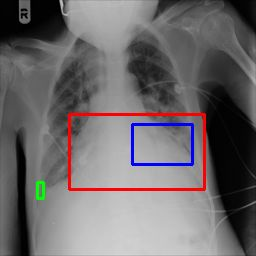

Deployments of artificial intelligence in medical diagnostics mandate not just accuracy and efficacy but also trust, emphasizing the need for explainability in machine decisions. The recent trend in automated medical image diagnostics leans towards the deployment of Transformer-based architectures, credited to their impressive capabilities. Since the self-attention feature of transformers contributes towards identifying crucial regions during the classification process, they enhance the trustability of the methods. However, the complex intricacies of these attention mechanisms may fall short of effectively pinpointing the regions of interest directly influencing AI decisions. Our research endeavors to innovate a unique attention block that underscores the correlation between 'regions' rather than 'pixels'. To address this challenge, we introduce an innovative system grounded in prototype learning, featuring an advanced self-attention mechanism that goes beyond conventional ad-hoc visual explanation techniques by offering comprehensible visual insights. A combined quantitative and qualitative methodological approach was used to demonstrate the effectiveness of the proposed method on the large-scale NIH chest X-ray dataset. Experimental results showed that our proposed method offers a promising direction for explainability, which can lead to the development of more trustable systems, which can facilitate easier and rapid adoption of such technology into routine clinics. The code is available at www.github.com/NUBagcilab/r2r_proto.